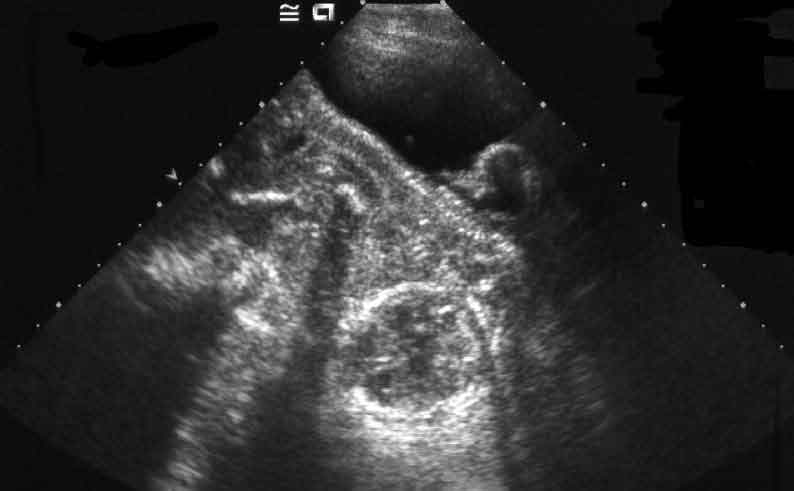

Perdere un bambino durante la gravidanza purtroppo non è un evento raro e deve essere considerato un vero e proprio lutto. In questi giorni i media si sono interessati a diversi casi di morte intrauterina avvenuti in alcuni ospedali italiani, sollevando spesso il sospetto di episodi di malasanità.